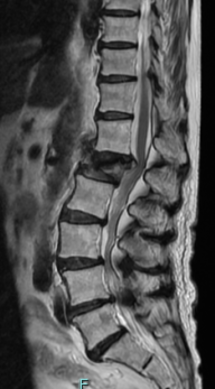

術前MRIでは脊柱管の狭窄を認め、神経の圧迫を認めています。後方からの除圧術後、神経への圧迫は改善しています。

近年は小さい傷で、内視鏡を用いた脊柱管除圧を積極的に行っています。